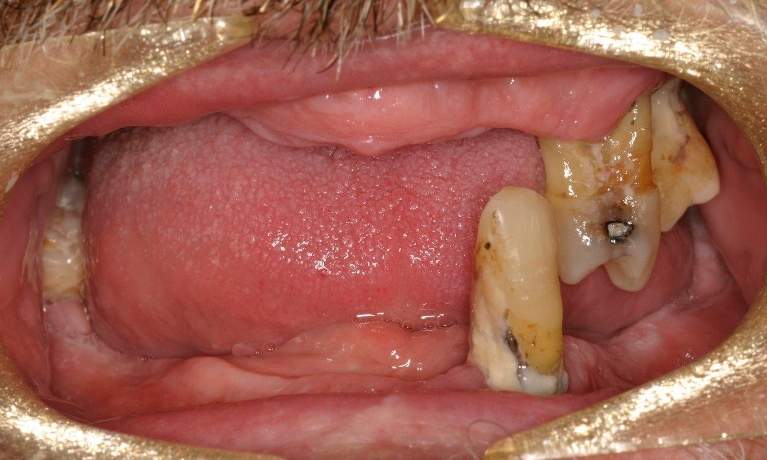

Perhaps one of the most critical decisions patients face is how to replace a missing tooth. We strive to save natural teeth when possible. Sometimes, however, tooth loss is unavoidable.

Dr Wong will begin by evaluating your oral health and bone quality. Dental implants need a stable foundation of healthy bone to secure them in place.

To determine whether dental implants are recommended, a complete oral evaluation will be necessary, which includes:

- Physical examination

- X-rays

- Medical history

If additional treatments such as bone grafting or sinus augmentation are required, we will arrange them to make dental implant treatment possible.